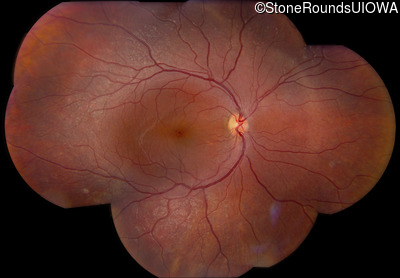

Fundus Photography - Right - 20/32 -1

Exemplar